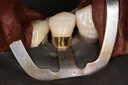

Scott Kanamori #3 finish